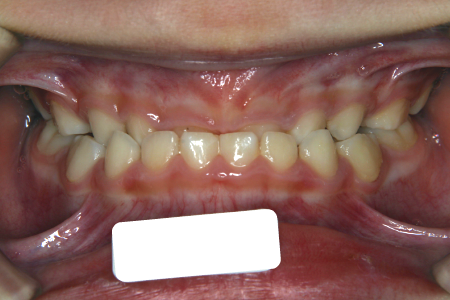

受け口 反対咬合 南千住の矯正歯科 南千住小児歯科矯正歯科 土日診療

受け口 子供 小児 こども歯並び治療室

7歳子どもの反対咬合 受け口 下顎前突 の症例

小児反対咬合 症状と治療 スマイルガイド 矯正歯科の正しい選択を応援するサイト

ささき矯正歯科 受け口 反対咬合 下顎前突

受け口 反対咬合 恵比寿 渋谷の矯正 矯正歯科なら恵比寿ますだ矯正歯科

受け口 反対咬合のお悩み 大阪矯正歯科グループ

受け口 反対咬合の矯正 期間 費用 東京の矯正歯科